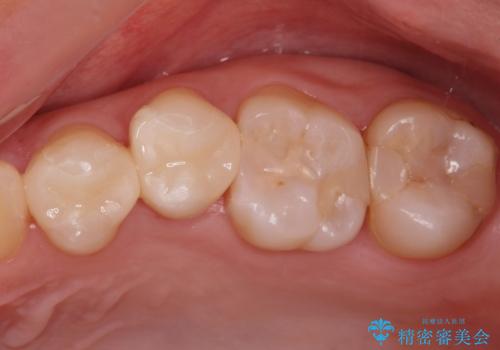

適合の良い詰め物が入りました。

虫歯がある状態で矯正を行うと矯正中に虫歯が悪化する可能性があるので先に治療を行なってから矯正をはじめます。

他の部位も治療予定です。